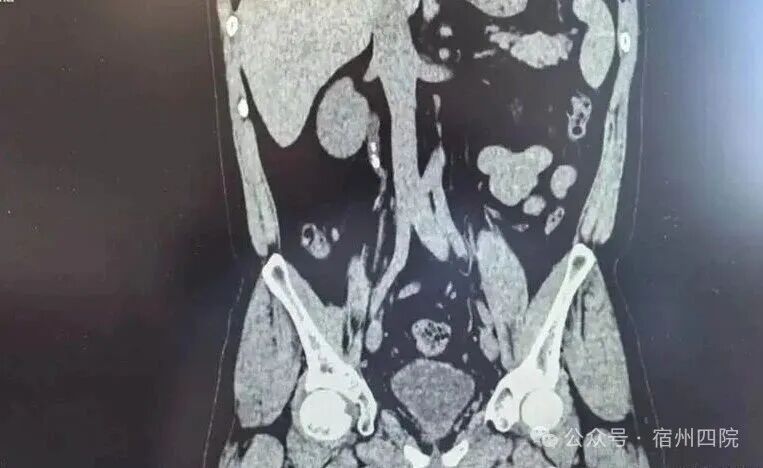

近日,我院泌尿外科为一位右侧尿管结石的患者实施了右侧经尿道输尿管软镜钬激光碎石术,术后次日患者复查无残石,顺利出院。

患者徐某,因结石症状未完全缓解,辗转至我院复查,门诊彩超提示右输尿管上段结石伴肾积水。面对这一情况,泌尿外科团队迅速评估,完善术前检查,排除手术禁忌症后,为患者实施了右侧经尿道输尿管软镜钬激光碎石术。术后次日复查无残石,患者顺利出院,对医院的诊疗技术、服务态度及设备先进性给予了高度评价。